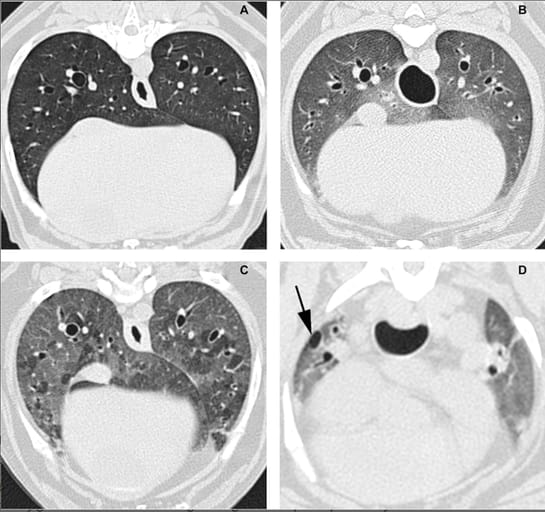

Thoracic computed tomographic images. (A) Normal dog graded as 0. (B) Generalized ground-glass attenuation graded as 1 (mild severity). (C) Generalized mosaic ground-glass pattern graded as 2 (moderate severity). (D) Focal honeycombing pattern in periphery of right cranial lung lobe (arrow) graded as 3 (marked severity) associated with focal adjacent bronchiectasis